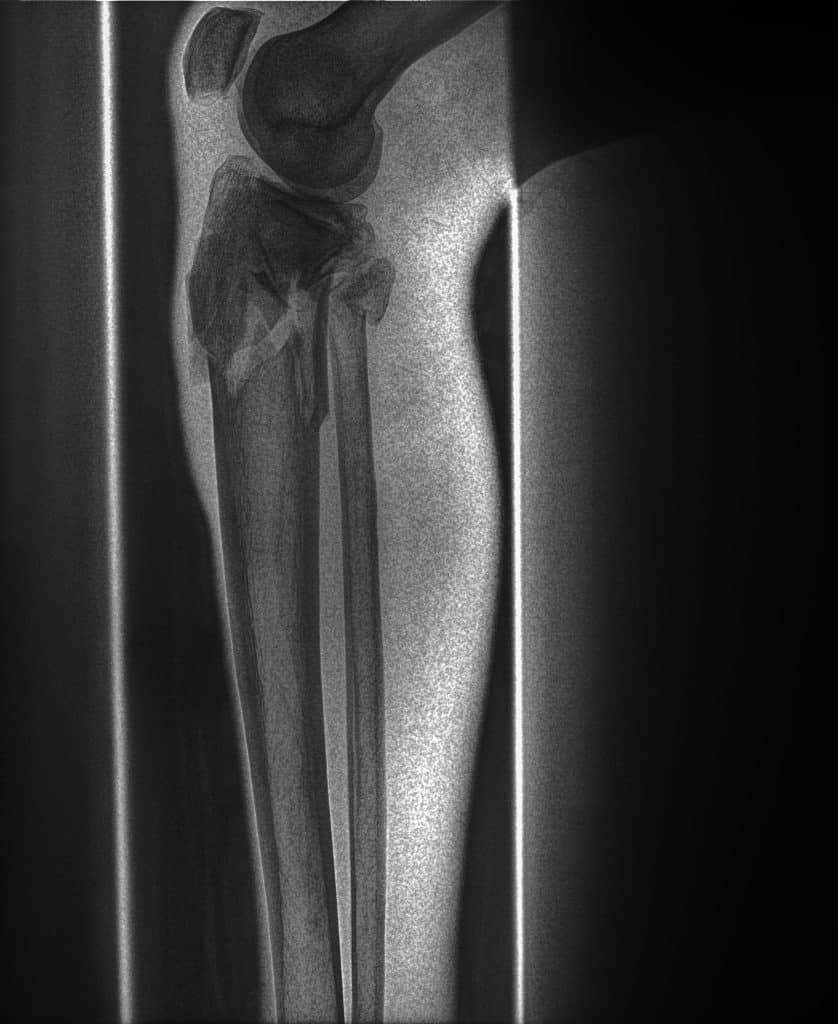

Bone images generated by spectral imaging emphasize calcified structures, allowing clinicians to review skeletal anatomy with reduced soft-tissue overlap.

The Bone image is more adept at presenting the bony skeleton in a manner that delineates it better than a conventional DR image. By displaying only on the areas of highest subject density, the SpectralDR™ technology yields improved visualization of both healthy and diseased bone.

SpectralDR bone images emphasize skeletal structures, allowing clearer visualization of the fracture compared with the conventional radiograph.